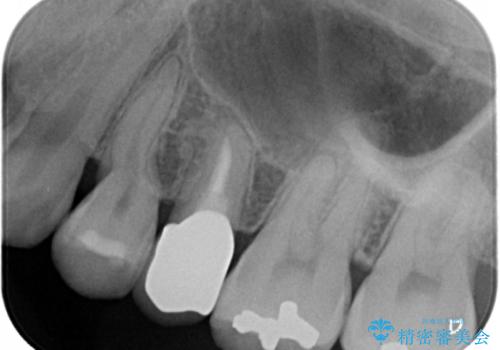

欠けている奥歯(左上5)は失活歯で、保険内の銀の詰め物(メタルアンレー)で治療されていました。

金属の詰め物と土台を除去し、ファイバーコア(金属を使わない強くてしなやかな土台)を植立したのちセラミッククラウンによる補綴治療を行いました。

精査したところ、右上の奥歯(右上5)に根尖病変を認めたため、こちらは根管治療後にセラミッククラウンによる補綴を行いました。